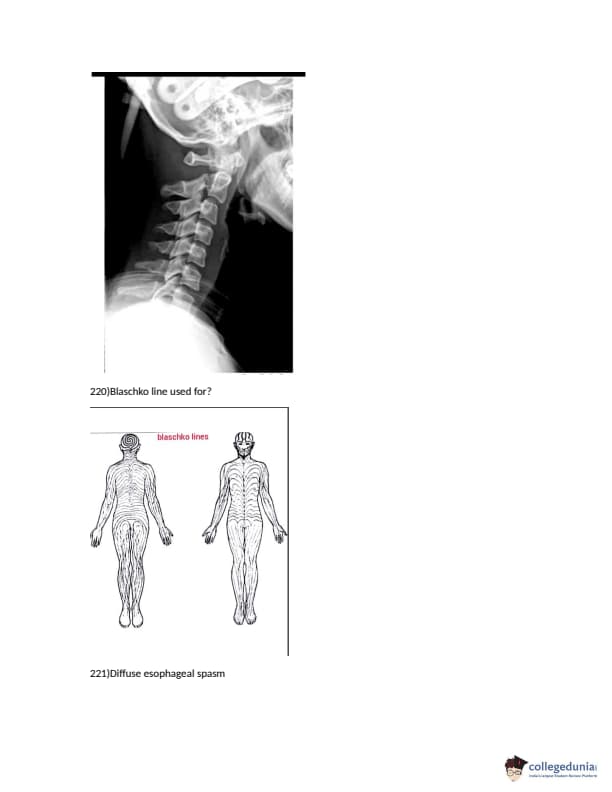

FMGE 2018 Question paper with answer key pdf conducted on December 14, 2018 is available for download. The exam was successfully organized by National Board of Examinations (NBE). The question paper comprised a total of 226 questions.